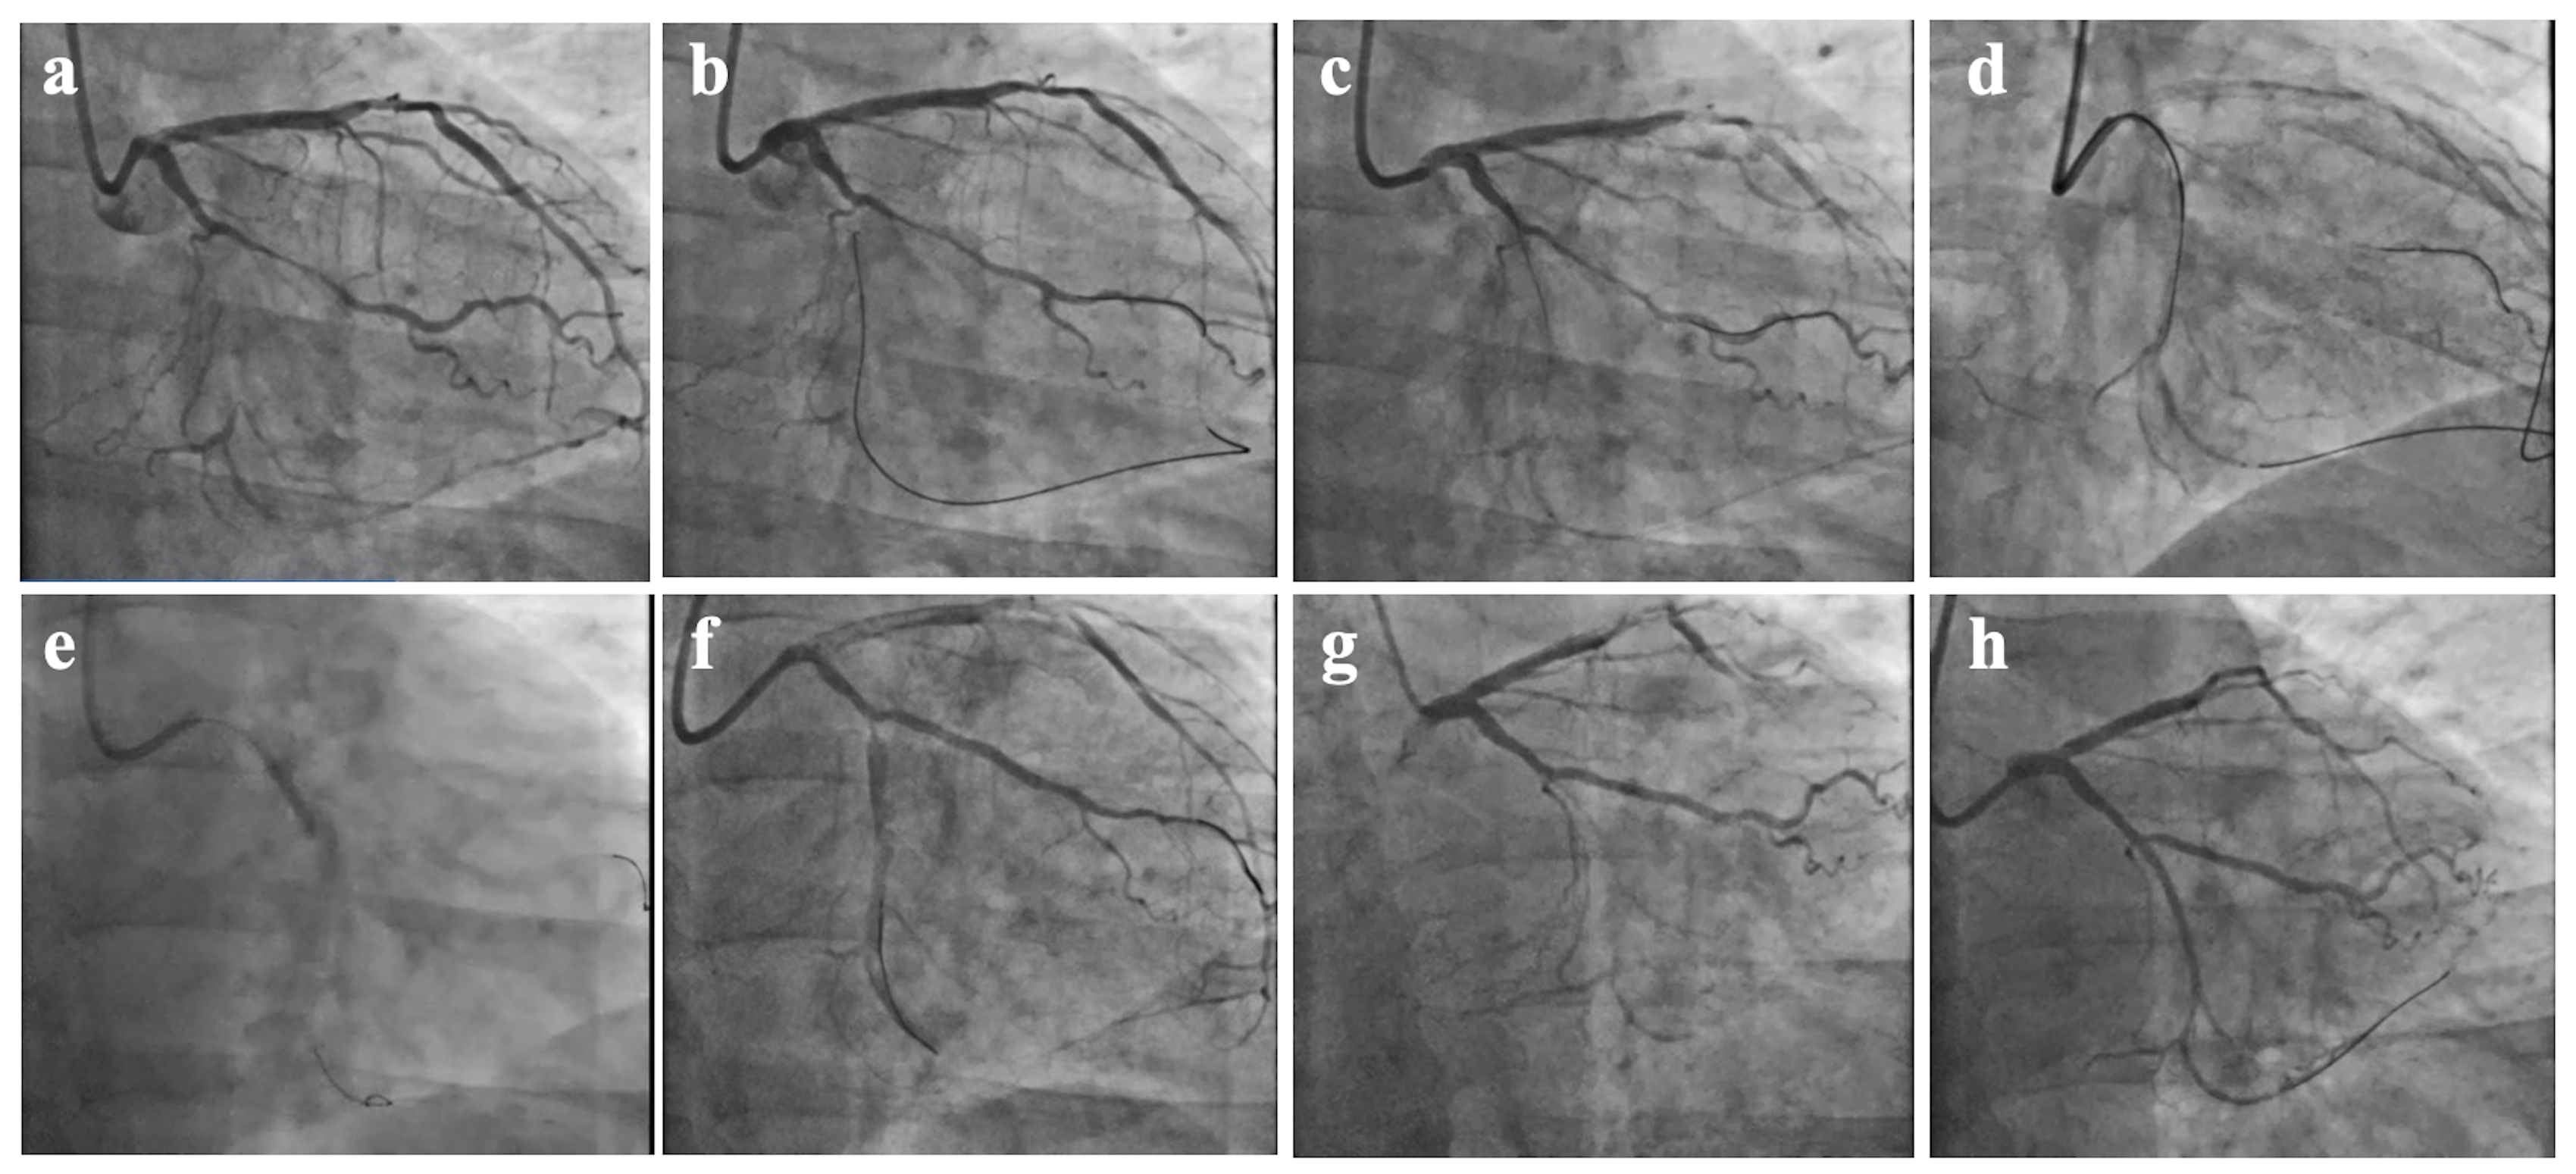

Zhong et al. [7] retrospectively analyzed 208 patients who underwent a failed CTO-PCI attempt and underwent a repeat procedure at the same cardiac center, among which 35 patients (16.8%) received SPM during the first attempt. They found that the interval between reattempts (increasing every 90 days) was inversely associated with the technical success rate of reattempts (OR: 0.85; 95% CI: 0.73–0.98; p = 0.030). Previous study [8] has shown that when the second attempt is over 90 days, the success rate decreased. This may be due to tissue proliferation and enhanced fibrosis during vessel healing, especially with medial or adventitial injuries [19]. Although 100% of patients were successfully opened within 60–90 days, only 2 of these patients underwent a second PCI. In 2020, Hirai et al. [20] conducted a study that focused on the impact of SPM in patients who underwent unsuccessful CTO-PCI. In their study, of all the patients who underwent the first CTO-PCI, 56 underwent a second angiography after the first PCI was unsuccessful. Of these 56 patients, a total of 31 (55.3%) underwent SPM. By comparison, only 44% of patients who underwent a failed CTO-PCI received SPM in our study. They found that the success rate of repeat CTO-PCI attempts was higher (87.1%) when the SPM procedure was performed at the index procedure. SPM was the only significant predictor of successful follow-up CTO-PCI attempts after an unsuccessful CTO-PCI attempt (Fig. 3). However, they did not specify the interval between the second surgery after SPM in their study. Our study found that attempts following 30–90 days after the initial procedure and SPM was a factor for the success of the second PCI attempt.

Fig. 3. CTO-PCI attempt, SPM procedure, and second operation at 65 days after SPM. (a) Chronic total occlusion of the distal portion of the LCX. (b) The first attempt to open the LCX CTO through the occluded segment via the ipsilateral collateral circulation using the retrograde approach. (c) The retrograde guidewire is located under the endothelium. (d) Antegrade Dissection Re-entry technique into the true lumen. (e) SPM along the antegrade guide wire. (f) Postoperative SPM. (g) Second time of CAG after 65 days. (h) The LCX-CTO was successfully opened in the forward direction, and the re-operation was successful after SPM. CAG, coronary arteriography.